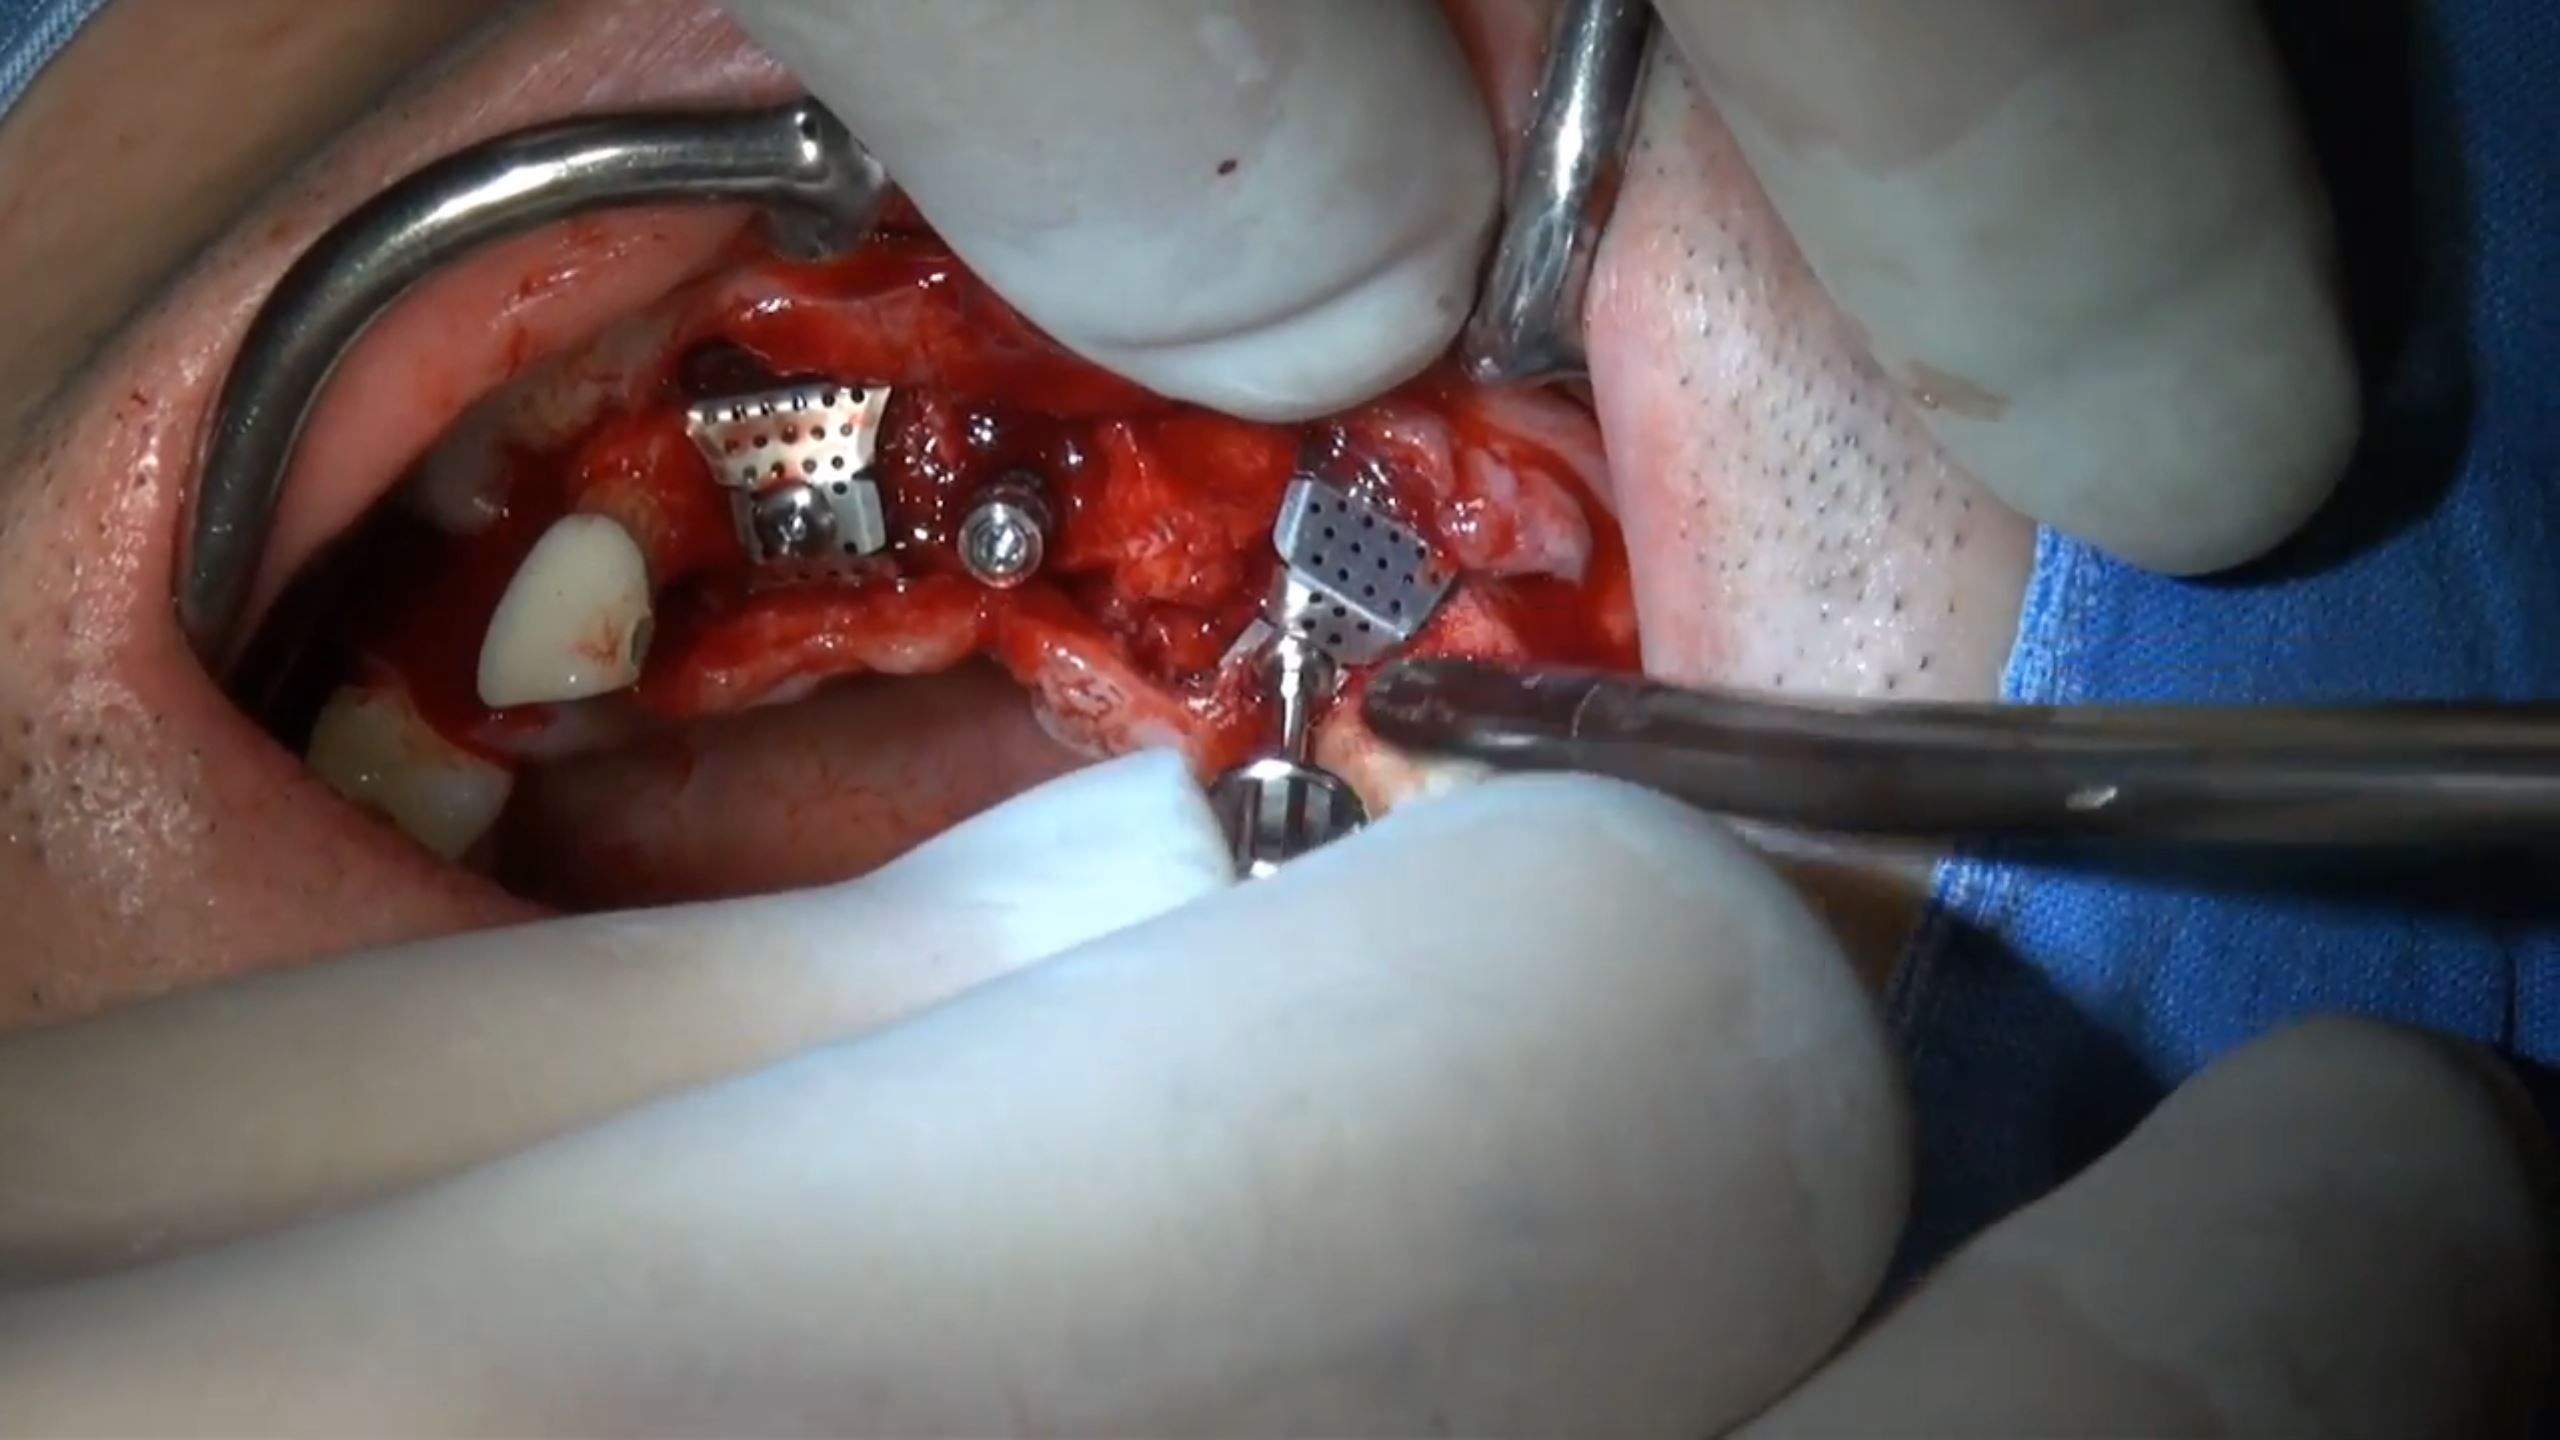

#11,#12,#23,#24 Root Membrane Technique with Digital R2GATE Surgery

Dr. Kwang Bum Park,Aesthetic zone,Digital Guided Surgery,Maxillary Anterior,Maxillary Posterior,#11,#12,#23,#24,Guided surgery,Root Membrane,AnyRidge,MiNi,R2GATE Guide,MEGA ISQ,Root Membrane Kit,R2GATE Surgical Kit(AnyRidge),Initial stability,Customized abutment,PMMA crown,Aesthetic…